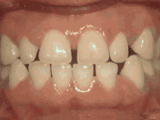

深覆合,咬牙时,上牙盖住下牙的部位过多,影响美观,经过矫正的牙齿是这样的~

深覆盖,咬牙时,上牙差不多完全把下牙挡住了,经过矫正后的牙齿是这样的~